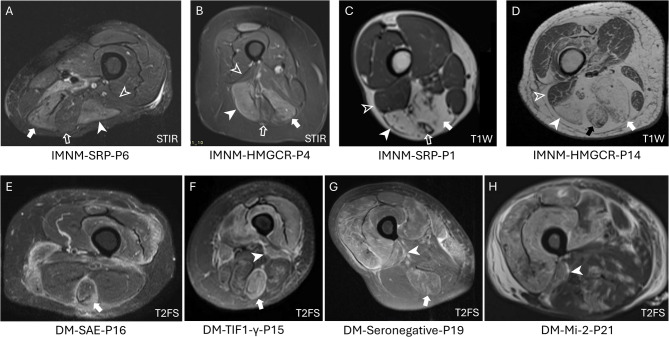

Results: The most affected muscles in IMNM were the semimembranosus (3.0 [2.7-3.0] {median [IQR]}), biceps femoris-long head (BF-LH) (2.7 [2.0-3.0]), and adductors (2.5 [2.0-3.0]). In DM, the most affected muscles were the vastus lateralis (2.7 [2.3-3.0]), vastus intermedius (2.9 [2.2-3.0]), vastus medialis (2.3 [1.7-2.7]), semitendinosus (2.2 [1.0-2.7]), rectus femoris (RF) (2.0 [1.0-2.8]), biceps femoris-short head (BF-SH) (1.9 [1.0-2.7]), gracilis, and sartorius. Intergroup statistical difference of scores was significant (p < 0.01) for 10/11 thigh muscles excluding the RF (p = 0.19), supporting an inverse relationship of muscle involvement for DM and IMNM. The secondary comparative analysis of only muscle edema scores was significant (p < 0.05) for the same 10/11 muscles with a consistent direction for all comparisons.

Conclusion: DM and IMNM affect disparate thigh muscles on MRI. DM preferentially affects the anterior thigh, semitendinosus and BF-SH in the posterior thigh, and gracilis in the medial thigh, whereas IMNM preferentially affects the posterior thigh (semimembranosus and BF-LH) and adductors in the medial thigh.